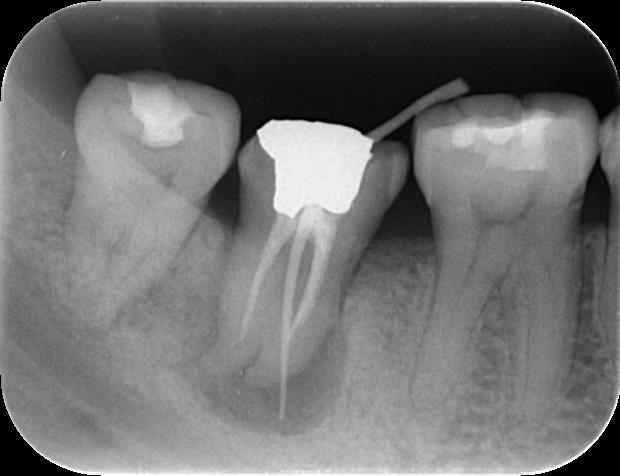

実際の症例

-

治療前

治療後

| 治療内容 | 精密根管治療 | 期間 | 3~6ヶ月※状態に応じて変わります |

|---|---|---|---|

| 治療回数 | 5回 | 費用 | 再根管治療170,000円(税込 187,000円) |

| リスク 副作用 |

歯質の状況に応じて抜歯の診断。もしくは歯根端切除に移行あり。 | ||